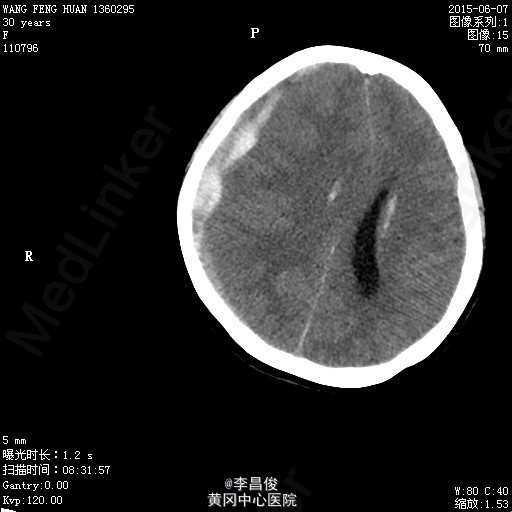

入院完善相关检查:血常规:血红蛋白 105.1g/L,血小板 95*10^9/L,尿常规:蛋白 -,肝功能:谷丙转氨酶 77.9U/L,尿酸 426.7umol/L,凝血机制:D-二聚体 2267ng/ml。 血脂:甘油三酯:3.31;低密度脂蛋白:5.46,甲功、心肌三项、心脏彩超正常, 给予对症处理,患者于6月4 日8:42分在会阴左侧切下以LOA位顺利娩出一活女婴,产程顺利,产时血压最高达160/110mmHg,给予心痛定一粒舌下含服,产后回病房后监测血压在100-140/70-90mmHg之间波动。6月7日5点多头痛明显,急查头部CT提示:右侧额颞顶部硬模下血肿。请神经外科急会诊,建议转专科治疗。转外科后,患者意识障碍加重,6月8日17:30时急诊全麻下行“右侧开颅硬膜下血肿清除+去骨瓣减压术”,术后转重症医学科。稳定后拔除气管插管后转回专科,行抗感染、止血、神经营养、脱水治疗,定期换药及CT复查,后出现癫痫发作,给予抗癫痫治疗。6月13日患者癫痫发作后呈持续状态,药物控制不理想,故转入ICU进一步监护治疗。患者神志昏迷,给予持续泵入丙戊酸钠、咪达唑仑控制抽搐,适当脱水、抗感染、营养支持及对症处理,并及时复查相关检查。患者癫痫控制后于17/6日顺利拔除气管导管。于17/6日再次癫痫发作1次,很快缓解。转神经科继续治疗:患者神志清楚,精神、食欲一般,诉左侧肢体无力伴麻木,无抽搐发作,右侧肢体肌力尚可,左侧肢体肌力3级。肌张力不高。继续给予抗癫痫、适当抗感染、肢体康复训练及对症支持治疗,一周后行颅脑MRI:未见明显异常;查体:心肺听诊(-),腹软,压痛反跳痛,双下肢无水肿,右侧肢体肌力尚可,左侧肢体肌力5级-,病理征(-),给予办理出院。

讨论:本病例中,右侧额颞顶部硬膜下血肿和妊高症二者哪个与癫痫发作的关系密切些?本病例如何下诊断更客观?欢迎大家讨论哈。